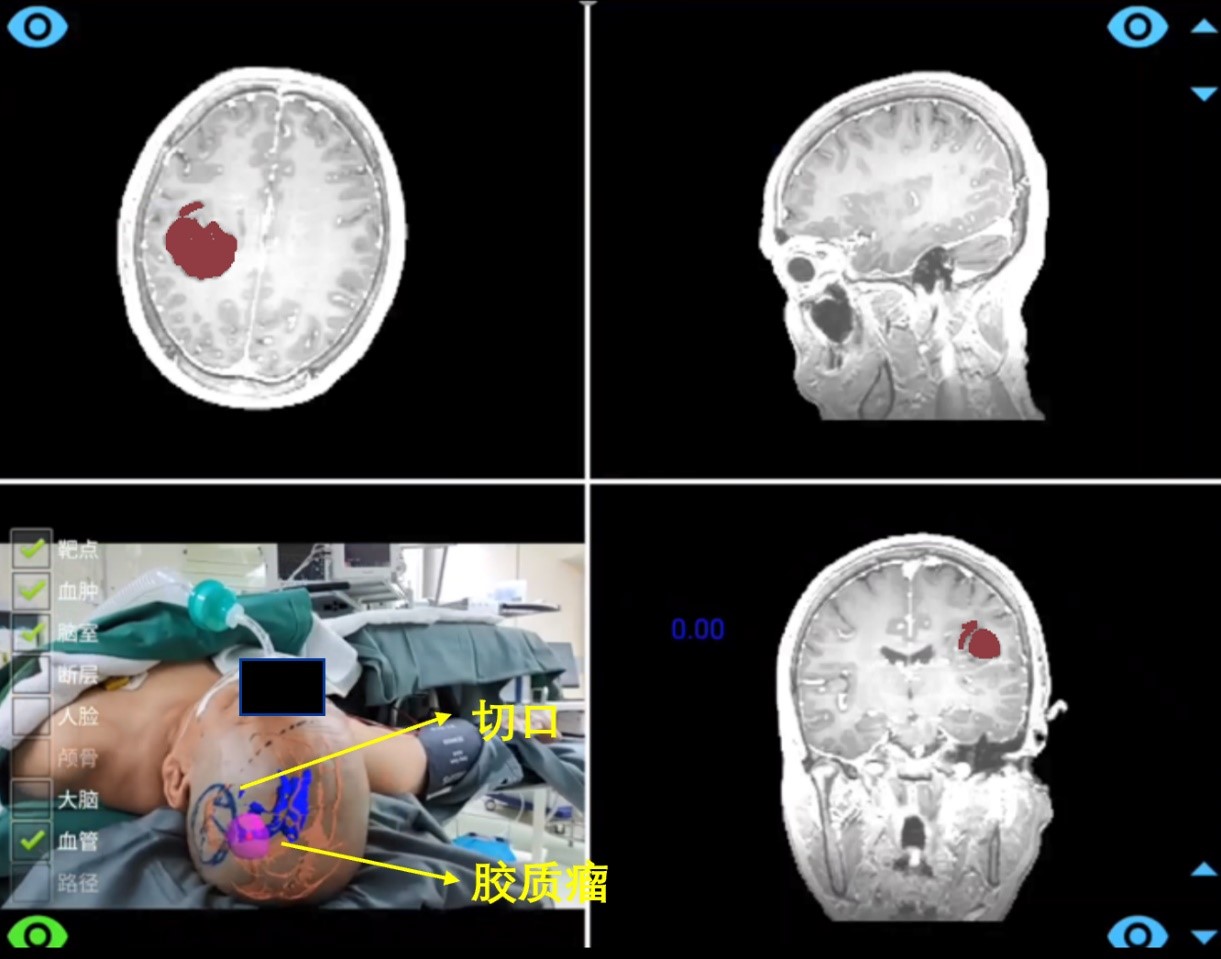

术中,通过SLAM跟踪可在无需头架和参考架情况下,实现增强现实导航。以一位胶质瘤患者为例,医生移动摄像头,系统可实时展示病人颅内的三维结构相对头皮的位置关系,辅助医生快速制定切口。

(术前切口制定)